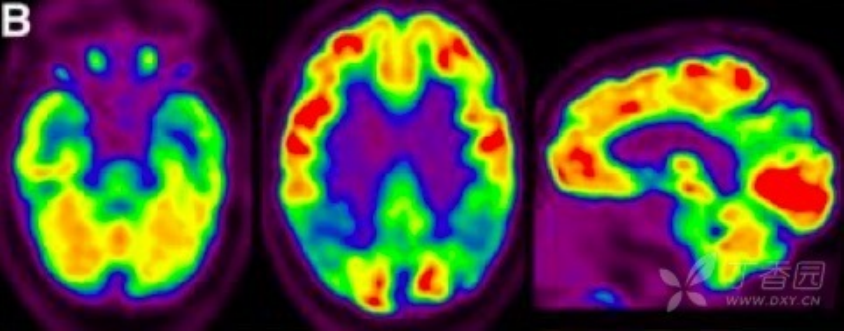

图 2 无症状健康对照组(HC)、MCI 和 AD 患者的 Amyloid PET 成像

2.葡萄糖代谢 PET(FDG PET) FDG PET 用于测量神经元和胶质细胞的葡萄糖摄取情况,被认为是突触功能变化最敏感的指标。AD 患者可出现典型的颞顶区、后扣带回皮质和楔前叶葡萄糖代谢降低,具有 90% 敏感性以识别出 AD 与其他类型痴呆。也有研究发现,AD 早期颞叶出现高代谢,提示可能为疾病早期代偿表现。携带载脂蛋白 APOEε4 等位基因认知正常受试者也被发现与 AD 相似脑区的代谢异常。因此,作为衡量脑功能改变的指标,FDG PET 对 AD 疾病进展过程中脑功能改变的评估诊断价值更高。

图 3 AD 患者的 18F-FDG PET 成像